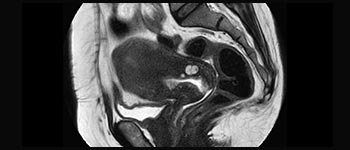

D.ssa Silvia Schiffer, Direttore e Senior Radiologo presso l'istituto Radiologie Schiffer in Germania, racconta le sue esperienze con il sistema RM Ingenia Prodiva 1.5T.

I primi utilizzatori di Ingenia Prodiva 1.5T raccontano le loro esperienze nell'uso del sistema e spiegano di come questo influisce sulle attività del centro diagnostico.